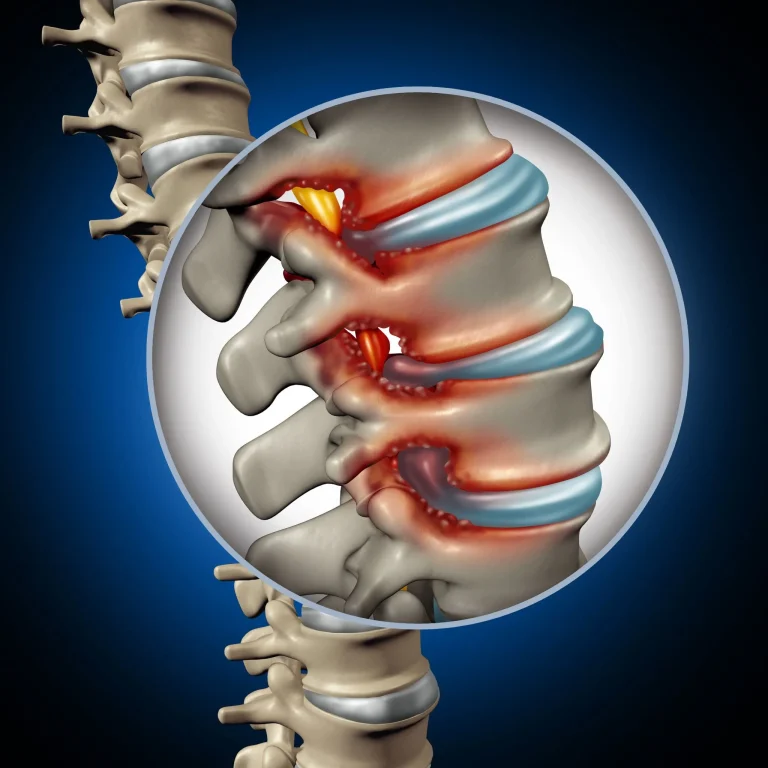

Illustration of an inflamed spinal section with highlighted vertebrae and intervertebral discs.

Stenosis Not Treated